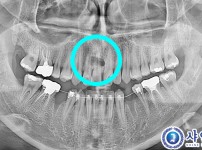

과잉치발치 - 구강외과전문의

해당 게시물은 의료법 제56조에 의거하여 로그인 후 열람이 가능합니다.